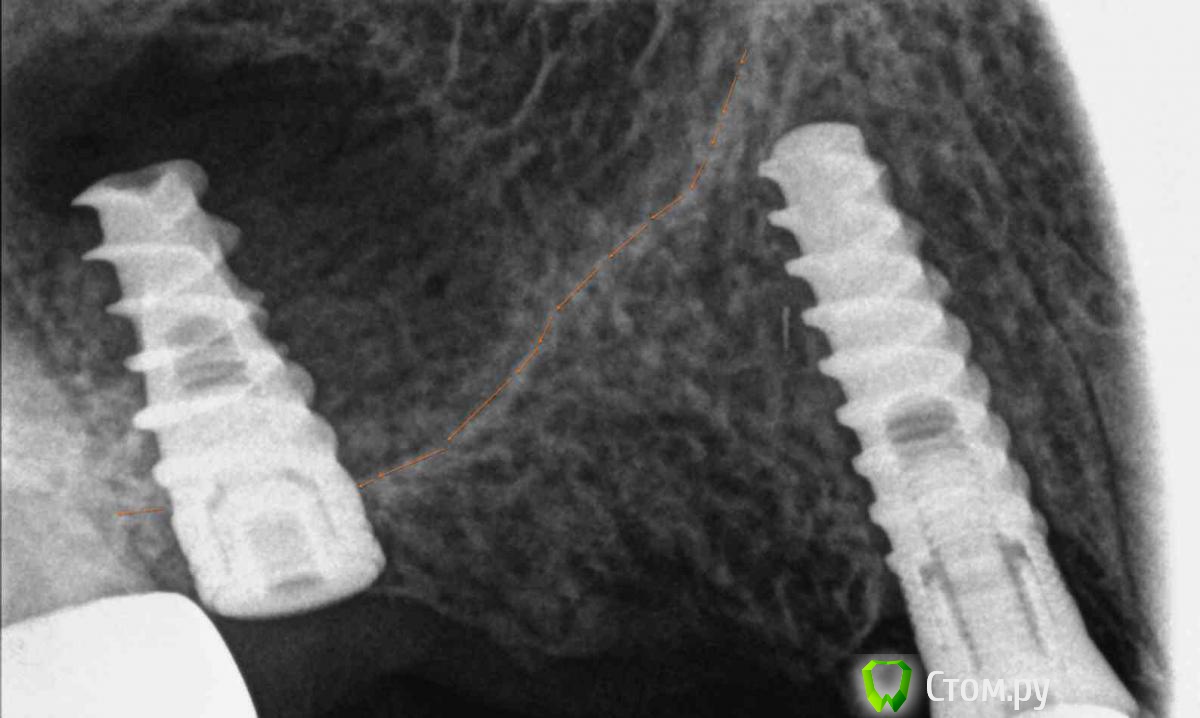

annda Опубликовано 22 апреля, 2014 Поделиться Опубликовано 22 апреля, 2014 Забыла пригрузить. 2 Ссылка на комментарий

CSS Опубликовано 22 апреля, 2014 Автор Поделиться Опубликовано 22 апреля, 2014 Забыла пригрузить. А это через какой период снимок? Ссылка на комментарий

annda Опубликовано 22 апреля, 2014 Поделиться Опубликовано 22 апреля, 2014 (изменено) Это сразу после постановки.Через 4 месяца есть ,с формирователями,где-то на сайте висит.Посмотрела,11го года работа,июль. Изменено 22 апреля, 2014 пользователем annda Ссылка на комментарий